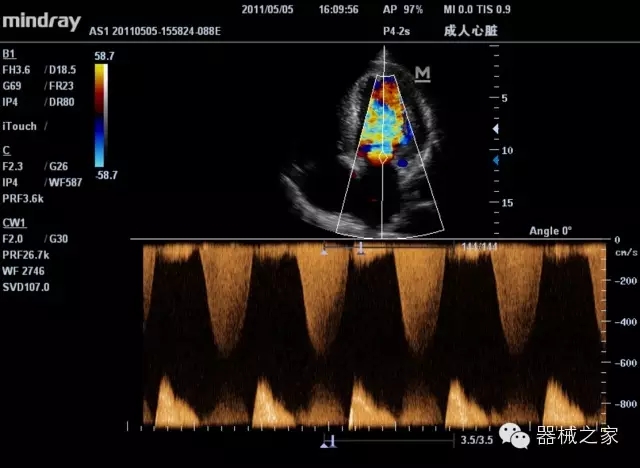

臨床圖片賞析

·優(yōu)秀的圖像效果、強(qiáng)大的功能體驗(yàn)、豐富的探頭選擇、合理的便攜式設(shè)計(jì),全中文顯示及病人管理界面,使得M7在任何場合、任何時(shí)候都能快速響應(yīng)更好的心血管、腹部、婦產(chǎn)、小器官等常規(guī)超聲檢查以及肌骨、神經(jīng)、顱腦、術(shù)中等新興領(lǐng)域的使用需求;

8倍波束并行處理系統(tǒng)

·在便攜式緊湊平臺上采用更多倍波束并行接收信號處理模式,無論二維還是彩色血流圖像狀態(tài)下,擁有更靈敏的回波頻移捕獲能力,大大提高時(shí)間分辨率,尤其使得心血管表現(xiàn)更為突出;